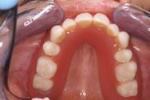

Implantaatbehandeling - prothese

Prothese

Indien er helemaal geen tanden en kiezen meer in de mond aanwezig zijn en men prothese dragend is, kunnen er implantaten geplaatst worden, waarop een  (nieuwe) prothese gemaakt kan worden. Dit wordt ook wel een klikgebit genoemd. De prothese zit dan weer vast en er wordt geen hinder/last meer ondervonden met bijvoorbeeld eten.

Prothese bovenkaak

Indien u een slechtzittende prothese heeft in de bovenkaak of u ervaart smaakverlies, dan kan in de meeste gevallen ook de prothese in de bovenkaak worden vastgezet middels implantaten. Meestal worden er dan vier implantaten in de bovenkaak geplaatst, waarop de uiteindelijke prothese geklikt wordt. Er zit dan geen plaatje meer in het gehemelte en u kunt met de tong weer het gehemelte voelen. Het eten smaakt beter en ook temperatuursschommelingen kunnen weer worden waargenomen. Voor het plaatsen van implantaten in de bovenkaak wordt in veel gevallen geen vergoeding door de zorgverzekeraar uitgekeerd. Alleen in enkele gevallen is vergoeding wel mogelijk. In het laatste geval is dit op indicatie en moet dit apart door ons worden aangevraagd bij de betreffende zorgverzekeraar.